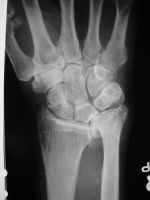

| Case 1. This 80 year old man developed wrist and elbow pain years after radial head excision for fracture. Radiographs show proximal migration of the radius resulting in valgus instability of the elbow, radiocapitellar impingement and distal ulnar impaction. This pattern of longitudinal forearm disruption, proximal radial fracture and dislocation of the distal radioulnar joint, is referred to as the Essex-Lopresti fracture dislocation. |